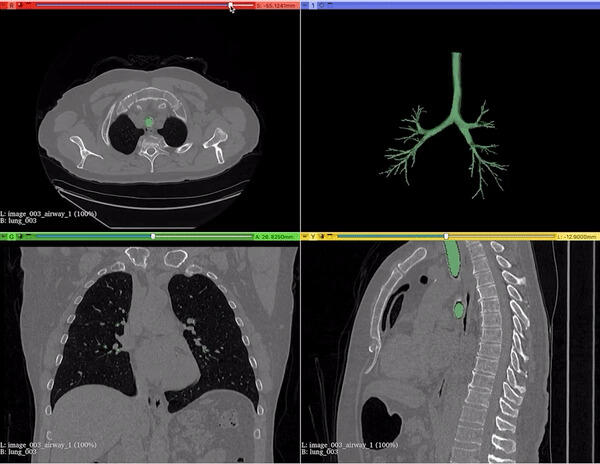

I’m a Senior AI Scientist at Johnson & Johnson. I have 8+ years of experience designing and deploying scalable, high-impact AI solutions in computer vision, multi-modal learning, and foundation models. I specialize in self-supervised learning, model compression, and multi-modal AI, driving state-of-the-art advancements in medical imaging and AI-powered drug discovery. I finished my PhD from Chester F. Carlson Center for Imaging Science at Rochester Institute of Technology (RIT), Rochester, NY under the direction of my advisor, Dr. Cristian Linte, funded by NSF and NIH grants. My PhD thesis focused on deep learning architectures for segmentation in medical imaging. I worked at Philips Research designing an optimized object detection framework for COVID-19 lung ultrasound, and at IBM Research on deep neural network pruning/optimization for explainable AI.

• Semantic & instance segmentation for medical imaging (2D/3D)

Deep Learning, AI & Computer Vision

3D CT Segmentation SAM / MedSAM Vision Transformers Self / Semi-Supervised

NiFTI File Viewer

macOS Compatible • Neuroimaging Utility

Designed and built a native macOS application to visualize NiFTI neuroimaging files, enabling intuitive exploration of volumetric medical data across coronal, sagittal, and axial planes.

Focused on performance, usability, and clean rendering for research workflows in medical imaging.

macOS Medical Imaging NiFTI 3D Visualization